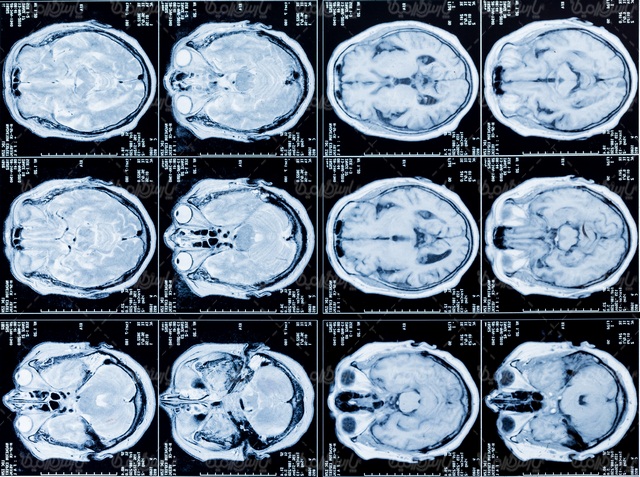

پژوهشگران از دانشآموزان این مدرسه اسکن امآرآی (MRI) گرفتند و همزمان، آزمونهای سنتی را نیز برای آزمایش دانش آنها برگزار کردند. آنها دریافتند که اسکن مغز بهتر از نمرات امتحان، میزان یادگیری دانش آموزان را پیشبینی میکند.

علاوه بر این اسکنهای امآرآی، جزئیاتی را در مورد «انتقال دور» (far transfer) نشان میدهند که یک نوع پیشرفته از یادگیری شناختی است که به فرد اجازه میدهد از دانش آموختهشده خود برای حل مسائلی استفاده کند که هرگز به او آموزش داده نشده است.